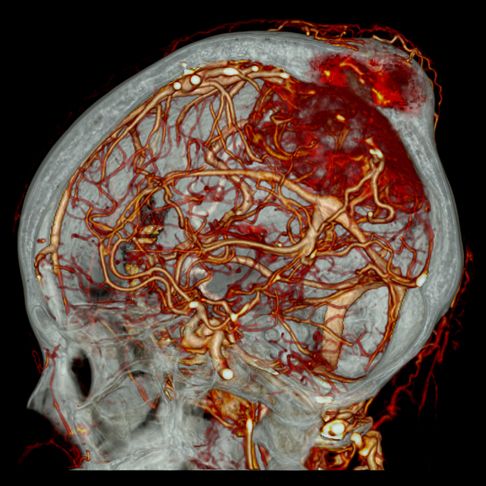

- КТ головного мозга – просматриваются структуры головного мозга, сосудистые сплетения, кости черепа и мозговые оболочки.

- Головы – черепа, придаточных пазух носа (ППН), орбит глаза, гипофиза, уха.

- Ангиография – аорты, сосудов, конечностей, шеи, головного мозга.

При подозрении на ишемический инсульт КТ является приоритетным методом диагностики. Внутривенное введение контраста позволяет не просто точно выявить очаг ишемии, с помощью него можно провести перфузионную КТ мозга, которая позволяет определить обратимость поражения ткани, установить давность инсульта, выявить коллатеральные пути кровоснабжения и определить поражение самых мелких церебральных сосудов.

КТ также легко выявляет гидроцефалию различного генеза. Признаками смешанной и наружной гидроцефалии является расширение субарахноидального пространства и желудочков (при смешанной), либо только субарахноидального пространства (при наружной).

КТ часто используют в диагностике энцефалопатии- органического поражения мозга различного генеза. Наиболее часто встречается дисциркуляторная (сосудистая) энцефалопатия. Признаками сосудистой энцефалопатии являются нарушение памяти, головные боли, головокружения, речевые нарушения, сонливость и др. КТ картина энцефалопатии включает в себя следующие признаки:

Аппарат МСКТ из-за короткого времени сканирования позволяет избежать подобных артефактов, а легкие теперь обследуются всего за одну задержку дыхания. Внедрение ЭКГ-синхронизации, при которой срез делается только между сокращениями сердца, а также использование контрастного вещества позволило детально обследовать сердце, аорту и другие «пульсирующие» сосуды. Главное, достигнуто высокое пространственное разрешение с возможностью сканирования в любой плоскости с построением трехмерных изображений, что позволило аппарату МСКТ показывать онкологию с точностью до 0,5 мм, исследовать даже самые мелкие метастазы и выявлять распространенность процесса.